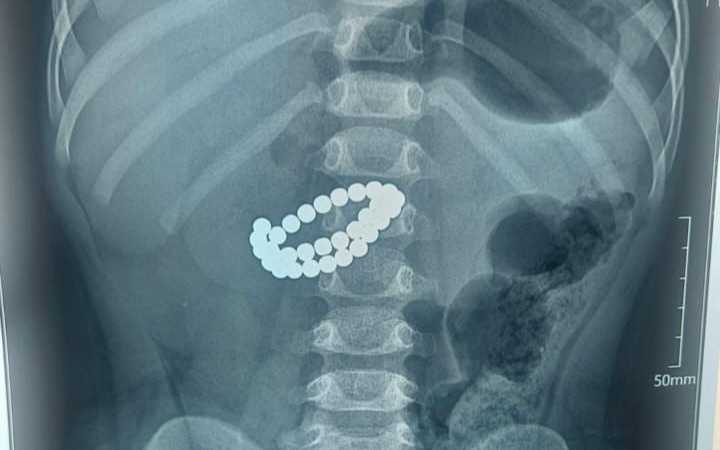

В Алматы врачи спасли жизнь ребенку в возрасте одного года и девяти месяцев, который проглотил 31 магнит, передает агентство Kazinform.

По информации управления общественного здравоохранения, малыш поступил в больницу в крайне тяжелом состоянии. Обследование показало, что в кишечнике находится большое количество магнитов. Врачи диагностировали множественные перфорации тонкой кишки и диффузный каловый перитонит.

Единственным шансом спасти ребенка стало экстренное хирургическое вмешательство. Хирурги провели срединную лапаротомию, извлекли магниты, ушили повреждения тонкой кишки, выполнили санацию и дренирование брюшной полости.